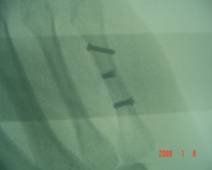

Fig.2 A e B: frattura diafisaria di falange prossimale tratta con viti.